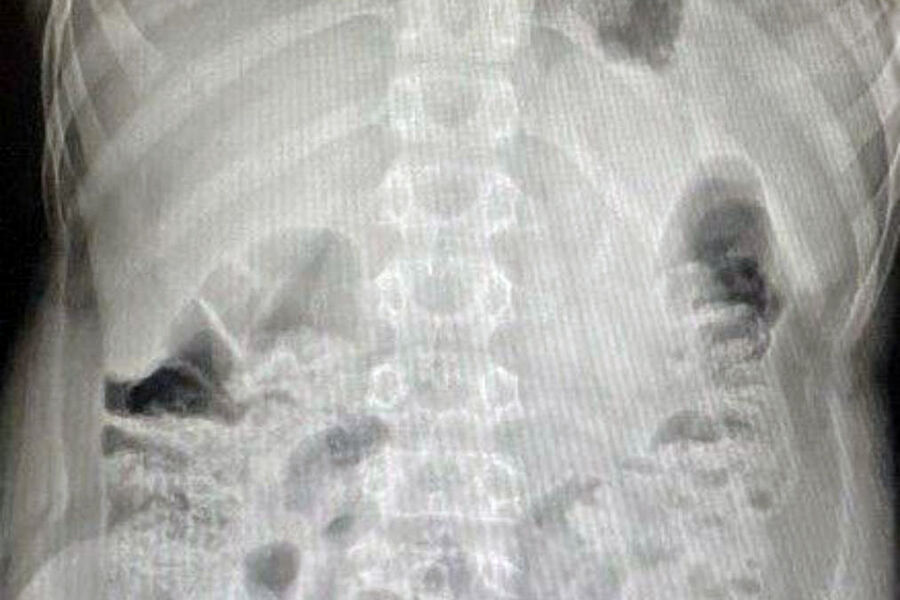

«Вначале выполнили лапароскопию, чтобы визуализировать как возможные осложнения, так и расположение инородного предмета. Затем провели эндоскопическое исследование, во время которого с помощью специальной петли извлекли литиевую батарейку», — поделился детский хирург, заведующий хирургическим отделением №1 Игорь Хворостов.

Врач добавил, что батарейка не успела окислиться, так что химического ожога удалось избежать. Мальчика выписали домой через два дня, как подчеркнули специалисты, полностью здоровым.